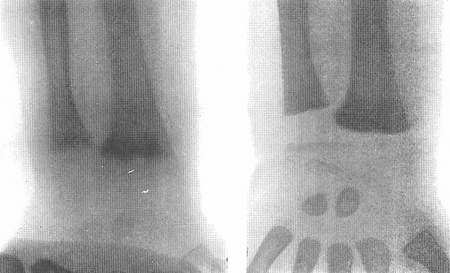

Radiografias de um punho de uma criança com raquitismo por deficiência de vitamina D antes (figura esquerda) e depois (figura direita) do tratamento com vitamina D

Do acervo de M.F. Holick, PhD, MD; usado com permissão